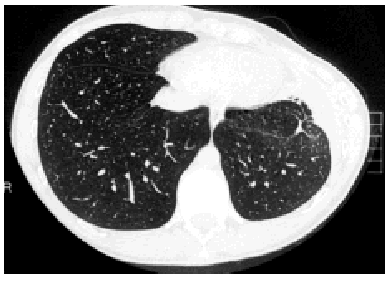

Figure. The thoracic computed tomography scan reveals retraction of the right hemithorax.

A 17-year-old male with no known relevant medical history diagnosed with a third recurrence of primary SP was admitted for definitive treatment by VATS, which was carried out with three trocars. The pleural cavity and the surface of the lung were carefully inspected and no resectable lesion causing the air leak was found. Pleurodesis was performed with 60 mg of a hydroalcoholic solution of povidone iodine instilled until a uniform distribution was obtained in the pleural cavity and across the surface of the lung. The patient had an uneventful postoperative recovery, did not present air leaks, and was discharged 5 days following the procedure. He was referred to respiratory physiotherapy because a small left pleural effusion was observed on the x-ray. The patient was well at early follow-up visits; he was also well by clinical standards at the 6-month visit and had apparently normal thoracic x-rays. However, he complained of a deformity in the operated hemithorax. Physical examination revealed a left-sided retraction and marked left-right asymmetry. A computed axial tomography scan (Figure) and magnetic resonance of the chest were obtained, and spirometry was performed. Both the computed tomography scan and the magnetic resonance image revealed posttreatment alterations in the pleura without pleural thickening, a small left loculated pleural effusion, a small scar-like infiltrate near the operated region, and a marked retraction of the left hemithorax. No muscular or osseous alterations of the thoracic wall that could have caused the retraction were found. Forced vital capacity was 4.19 (86%) and forced expired volume in 1 second was 3.79 (92%). Complete biochemical analyses with immunological studies were requested and were normal. Based on clinical course and complementary test findings the diagnosis was asymmetry of the thoracic wall due to surgery.